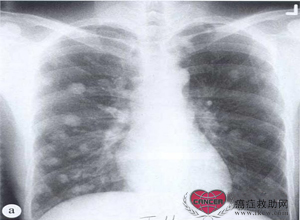

肺转移。(a)一位20岁亚洲男性肝细胞癌患者,胸片示肺内界限清楚的转移性结节。(b)病情在两个月内急剧恶化。虽然肝细胞癌的转移不常见,但也可见转移到骨、肺和脑。